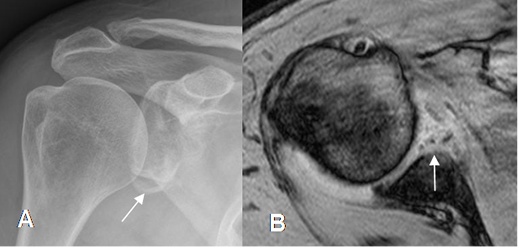

Fig 65. Lesión de Bankart óseo.

A: Rx AP. Signos de luxación anterior.

B: TAC axial y C: TAC reconstrucción coronal. Fractura del reborde antero-inferior de la glenoides, con fragmentos sueltos, por bankart óseo.

Fig 66 A. Lesión de Bankart óseo.

A: Rx AP. Después de la reducción de una luxación anterior, existe alteración en el borde inferior de la glenoides.

B: RM axial en FFE. Lesión del labrum anterior y reborde anterior de la glenoides, por Bankart óseo.